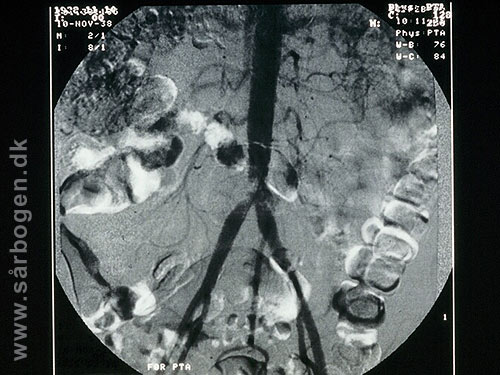

Før PTA af iliacakar...

Zoom

Under PTA af iliacak...

Efter PTA af iliacak...